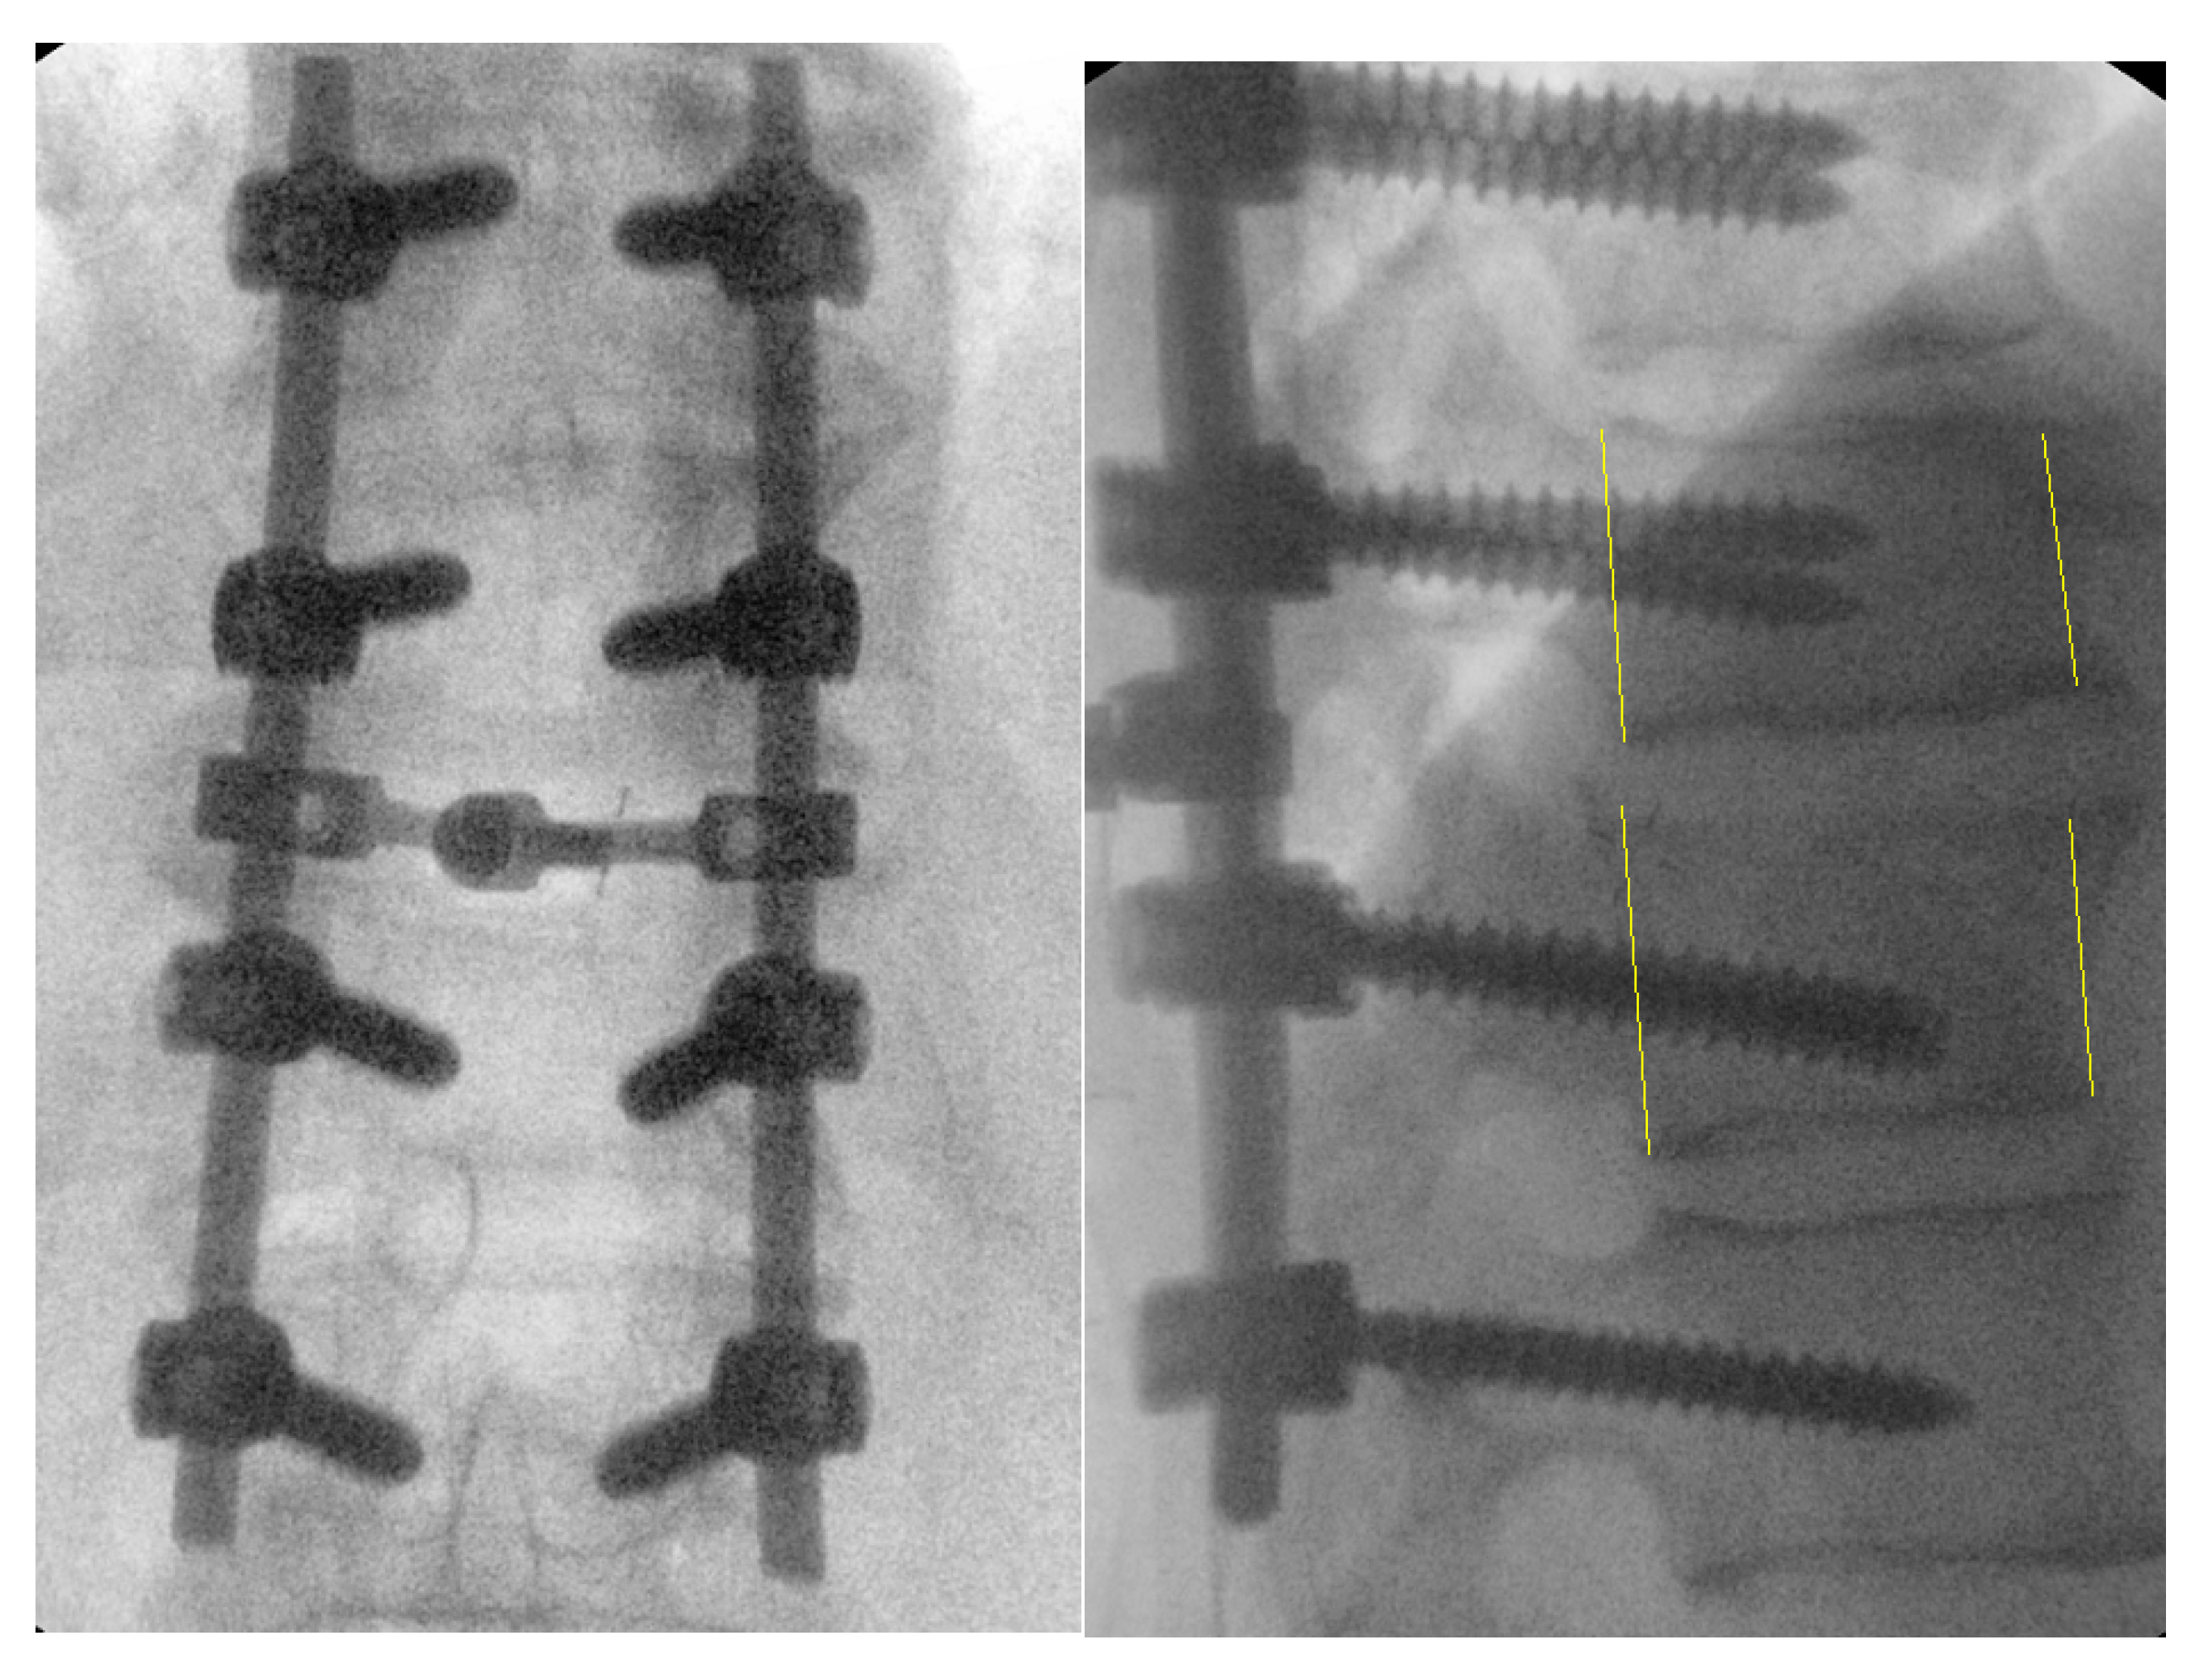

Figure 6. Intraoperative fluoroscopic images after successful reduction, decompression, and posterolateral fusion of Th10-L1.

This modified novel reduction technique was performed in 4 cases presenting with thoracic fracture-dislocations with complete paraplegia. The mean age of the patients presented was 32.2 (±7.1) years. All the patients presented in complete paraplegia. All the patients were operated as early as possible with mean time to surgery of 1.5 (±0.5) days. Upon utilization of the above-mentioned technique, we did not experience any technical difficulties in carrying out the reduction, and the post-operative period was uneventful in all the cases without any intraoperative complications such as dural tears or screw failure (Figure 6,7) [7]. The reduction was smooth, and we managed to avoid a 'second hit' to the already damaged spinal cord. (Figure 8) Due to the extreme compression of the spinal cord that occurs with spinal dislocation, patients remained paralyzed on follow-up visits until one year, although they did not experience back pain.